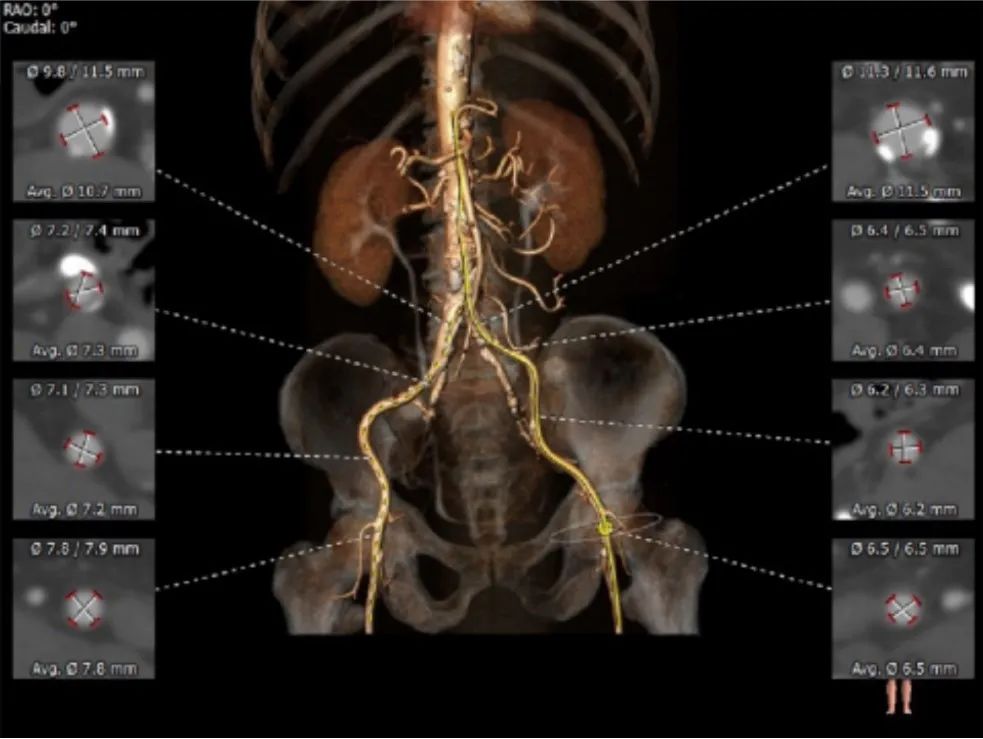

外周血管及主动脉弓解剖:

入路血管扭曲,双侧血管内径良好,所见主动脉血管壁显著钙化。

患者入路血管轻度扭曲,双侧血管内径良好,腹主动脉下段瘤样扩张。术中选择右股动脉为主入路,左侧位辅入路,手术过程要谨慎、轻柔,避免入路血管及腹主动脉瘤并发症。